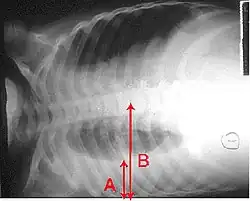

Derrame pleural é a acumulação excessiva de fluido entre as membranas que envolvem o pulmão (cavidade pleural). Uma quantidade excessiva deste fluido pode descompensar a ventilação por limitar a expansão dos pulmões (atelectasia).

Normalmente as membranas que envolvem os pulmões (pleuras) possuem apenas uma quantidade mínima de líquido pleural para evitar o atrito entre si. Quando uma dessas pleuras sofre com processo inflamatório causa dor torácica. Em função do comprometimento pleural ser evolutivo, tem-se produção anormal do líquido pleural e/ou redução na reabsorção deste líquido, que passa a acumular-se no espaço pleural e “afasta” uma pleura da outra, evitando o atrito, atenuando e até fazendo desaparecer a dor.

A produção aumentada e/ou a reabsorção reduzida faz com que haja uma grande quantidade de líquido no espaço pleural. Grandes derrames pleurais causam insuficiência ventilatória restritiva que se manifesta por “falta de ar” (dispneia).